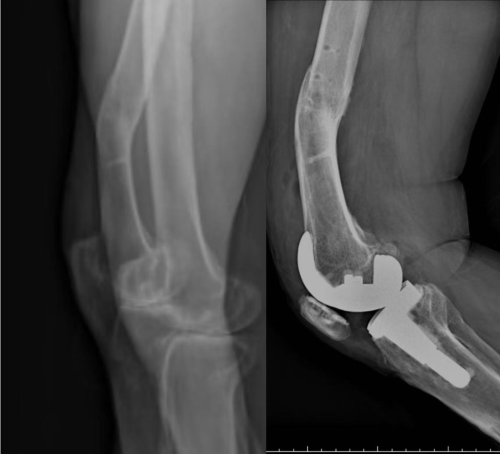

患者右膝长期呈内翻状态,行走跛行多年,同时伴有严重骨关节炎。更复杂的是,他早年曾发生右胫骨骨折,虽已愈合,但遗留骨骼畸形,导致膝关节解剖结构异常,传统手术难以精准恢复下肢力线。

图:术前术后X片对比

术后影像显示,下肢恢复至正常范围,假体安放位置与术前规划高度一致。患者疼痛明显减轻,目前已能自主站立并进行基础行走训练。